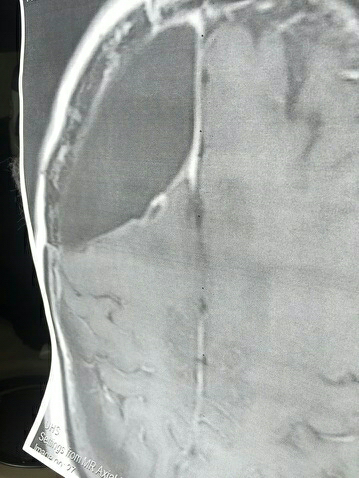

Medical Imaging Shared for Context

Medical imaging alone does not establish causation, treatment effect, or clinical outcome.